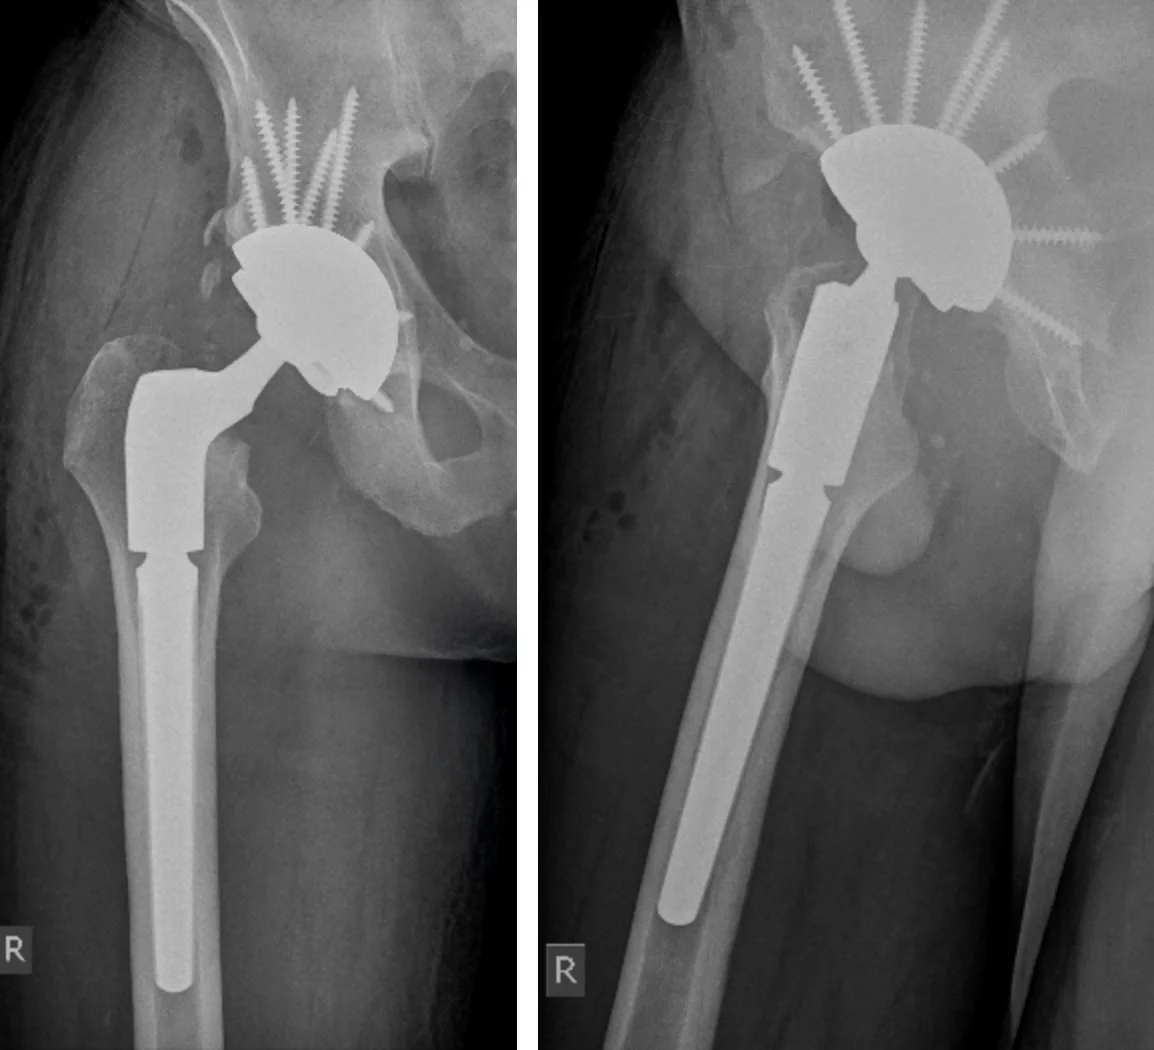

A revision hip replacement is an operation performed when your original hip replacement no longer works properly. This may involve removing some or all of the old implants and replacing them with new components. Unlike a first-time (primary) hip replacement, revision surgery is often more complex. This is because there may be scar tissue, damaged bone, or infection that needs to be carefully managed. In some cases, bone grafts or special implants are used to rebuild and stabilise the hip.

If bone has been lost, it may be rebuilt with bone grafts, metal augments, or specialised implants. Soft tissues around the hip are balanced to restore stability.

Stronger and often larger revision implants are used. These may be secured with screws, bone grafts, or other fixation methods for added stability.

• Reconstruction of the hip with new implants, which may be larger or reinforced with screws, augments, or bone grafts.

• The hip joint is reconstructed with new prosthetic components, designed for stability and function, usually requiring longer and bigger implants with additional screw fixation, augmentation or bone grafting if there has been bone loss.